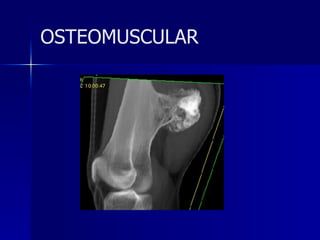

Fractura platillo tibial OSTEOMUSCULAR